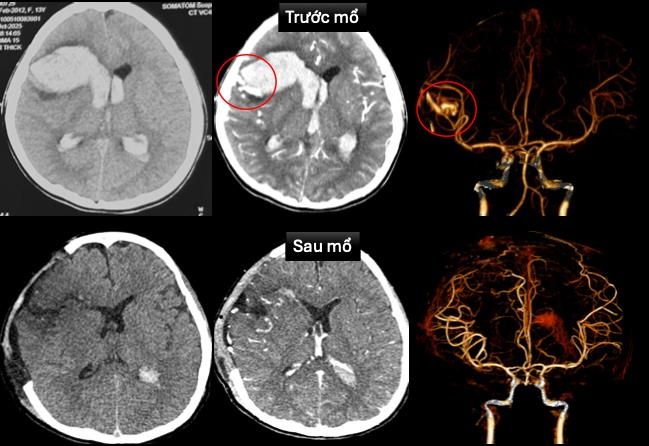

Sau phẫu thuật, bé được điều trị hồi sức tích cực, thông khí cơ học, dùng thuốc vận mạch và chống phù não. Hiện, bệnh nhi đã tỉnh táo, chỉ còn yếu nhẹ chân phải, tim mạch ổn định. Hình ảnh chụp não sau mổ cho thấy không còn dị dạng mạch, chức năng tim cải thiện rõ. Bác sĩ Huy tiên lượng bé có khả năng hồi phục tốt, không di chứng.

Hình ảnh chụp cắt lớp vi tính sọ não và dựng hình mạch máu não trước và sau mổ. Ảnh: Bệnh viện Nhi đồng 1